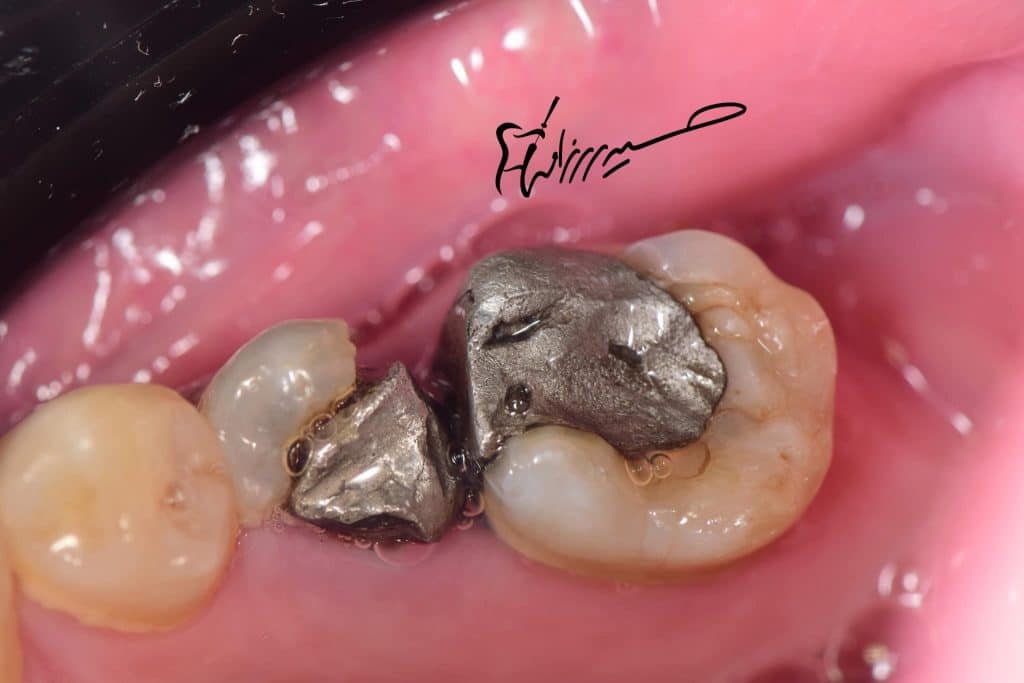

The tooth with large defective amalgam restoration ,

Fractured premolar with defective amalgam restoration and contact of both premolar and 1st molar .

Remove the old defective filling from tooth n.35 and also no.36 (overhanged!).